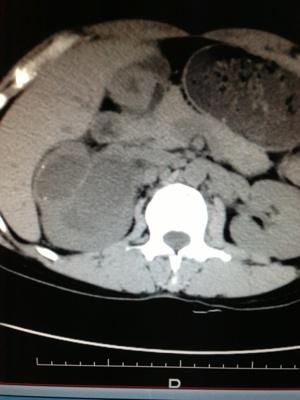

左肾脓肿(附图)

图片尺寸904x925